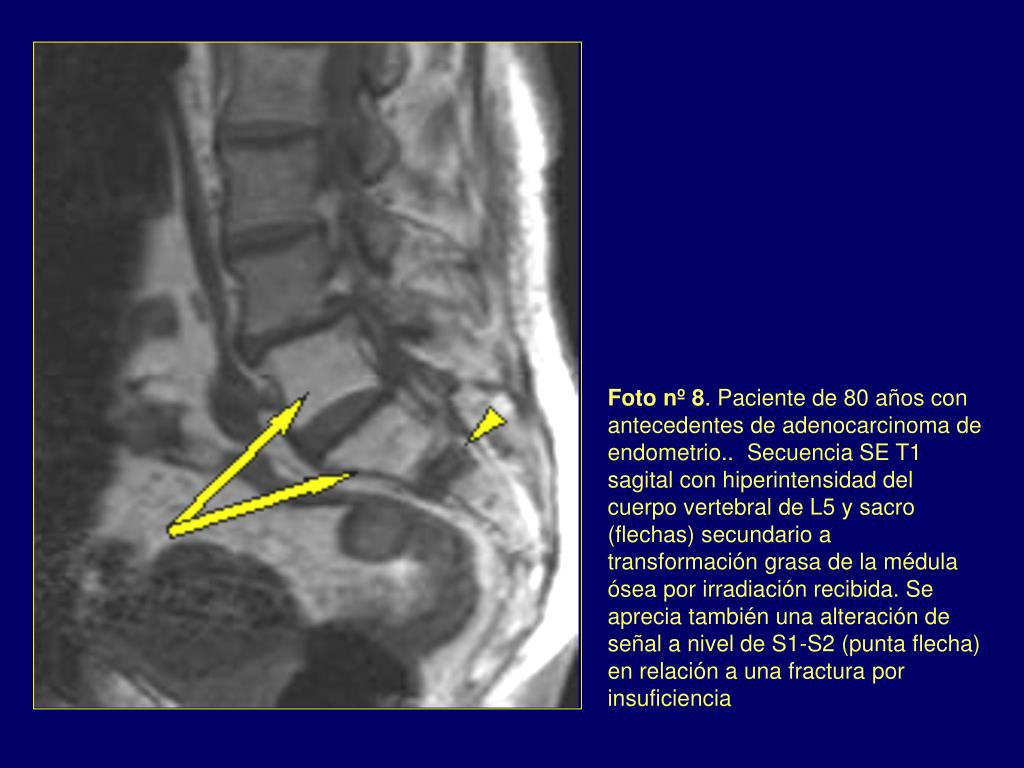

8. Foto nº 8. Paciente de 80 años con antecedentes de adenocarcinoma de endometrio.. Secuencia SE T1 sagital con hiperintensidad del cuerpo vertebral de L5 y sacro (flechas) secundario a transformación grasa de la médula ósea por irradiación recibida. Se aprecia también una alteración de señal a nivel de S1-S2 (punta flecha) en relación a una fractura por insuficiencia